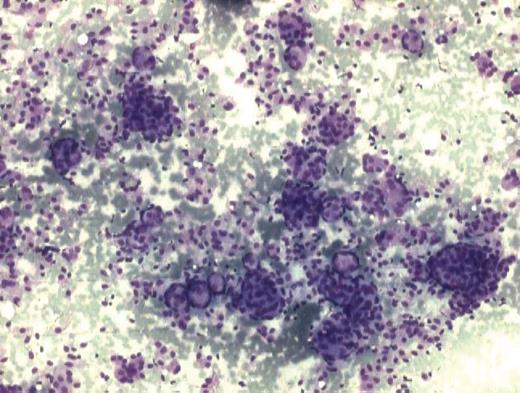

An 18-year-old female presented with a complaint of swelling below the angle of mandible on the right side which was associated with difficulty in swallowing since the last 3 months. Local examination revealed a swelling measuring 1.5 × 1 cm which was firm, fixed, non-pulsatile, non-transilluminant and non-tender. Oral cavity examination revealed a swelling of ∼1.5 cm diameter seen on the right side of the oropharynx. Computer tomography (CT) revealed that swelling is due to a heterogenous enhancing mass in parapharyngeal space with foci of calcification. The mass was not having any intracranial extension. The patient was subjected to fine needle aspiration cytology (FNAC) and the aspiration from the swelling yielded very low cellularity. A repeat FNAC with an intraoral approach was performed. Smears revealed loose cohesive clusters of cells in syncytial fragments along with concentric whorling pattern at places (Fig. 1). These cells were oval-to-spindle shaped with elongated nuclei having bland nuclear chromatin. At places, these cells had palisaded appearance with fibrillary pink substance. Singly scattered cells and myxoid substance were also observed in the haemorrhagic background. Occasional psamomma bodies were also discerned at places in the smears (Fig. 2). A cytological diagnosis of spindle cell lesion of neural origin with the closest resemblance of ectopic meningioma was rendered. The tumour was excised and subjected to histopathological examination. Microscopically, tumour was composed of oval-to-spindle cells with indistinct outline and eosinophilic cytoplasm. The nuclei were round to oval with homogenous chromatin. No mitosis was observed. In some areas, cells were arranged in whorling pattern. Numerous psamomma bodies were also noted (Fig. 3). The cytological diagnosis of extracranial meningioma was confirmed on histopathology. The patient is on regular follow-up without any complication.

Cytology smear showing cells arranged in loose cohesive clusters with whorling pattern at places. (MGG stain ×100).